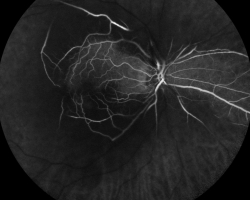

- Angiographie à la fluorescéine

- Retard de remplissage artériel (1min26 et 2min24) sauf au niveau des artères cilio-rétiniennes à droite

- Remplissage normal à gauche